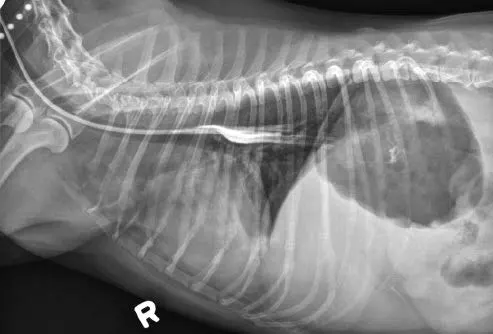

Tubes can be accidentally misplaced in the trachea (Figure 2A), nasopharynx, or nasal cavity, and subsequent feeding may result in aspiration pneumonia; therefore, appropriate placement should be confirmed before feeding is initiated. Various inexpensive methods can help verify tube location: laryngoscopic visualization of the tube entering the esophagus; suction to verify negative pressure; air infusion while auscultating the abdomen for borborygmus; infusion of sterile saline or nonionic contrast medium (Figure 2B), which sometimes elicits a cough with tracheal placement; or pH assessment of fluid aspirated from the tube.

Inadvertent placement of an NG tube in the trachea and bronchus of a miniature dachshund (11 years of age). This dog had a severe pulmonary interstitial pattern secondary to infusion of 20 mL of sterile saline through the tube; it had no cough reflex during infusion (A). After injection of 3 mL of iohexol 240, positive contrast medium outlined the alveoli, particularly in the caudodorsal thorax, confirming tube misplacement (B). The following day, radiography confirmed that contrast medium and saline had been cleared from the lungs.